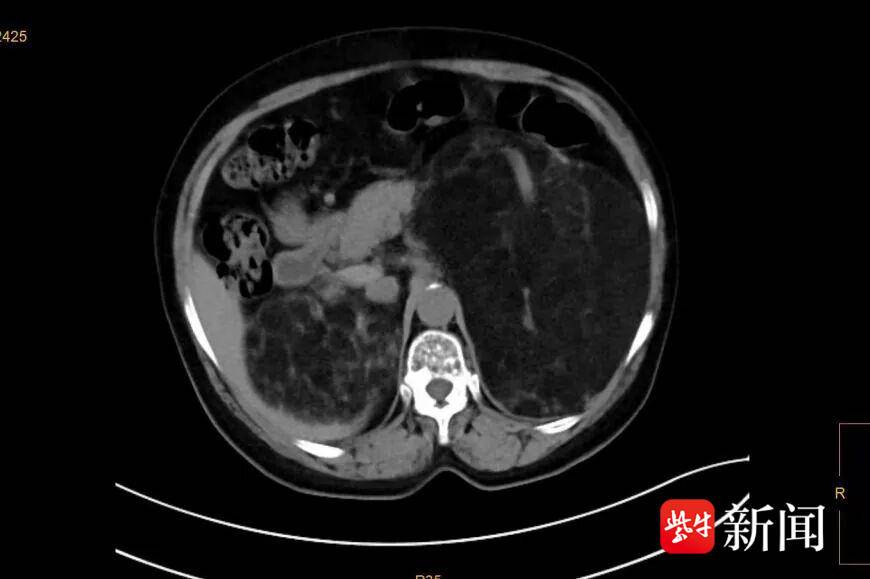

患者CT显示错构瘤巨大。通讯员供图

腹部CT检查发现,李阿姨的肾脏内有约25cm*18cm*18cm大小的错构瘤,它就是导致患者腹痛腹胀的“罪魁祸首”。“这种肿瘤多为良性,但瘤体巨大,已经严重压迫到腹腔内的其他脏器,如果瘤体一旦破裂,患者随时可能有生命危险。”该院泌尿外科主任医师王荣博士介绍。